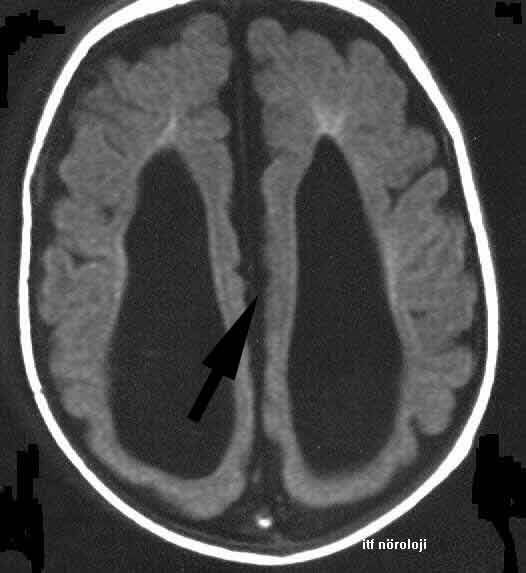

HG/KORPUS-KALLOZUM.jpg